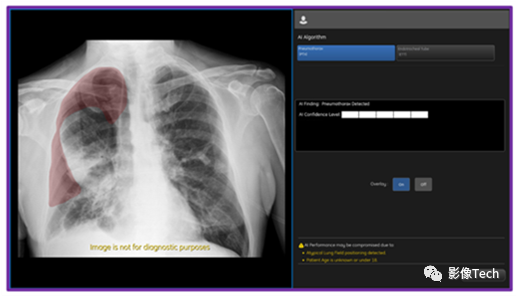

北美放射学会年会RSNA2023期间,GE医疗(纳斯达克股票代码:GEHC)宣布Critical Care Suite 2.1算法获批FDA 510 (K)。Critical Care Suite 2.1是一套用于自动分析正面胸部X射线影像(从数字X射线系统上采集)的AI算法,可以部署在多个计算平台上,包括PACS、本地、云端以及X射线成像系统。Critical Care Suite 2.1是Critical Care Suite算法系列的最新版本,能够检测和定位气胸(气体进入胸膜腔造成的积气状态)的位置。原来的算法已经能给疑似气胸的危重病例进行优先级排序。

现在一旦AI算法检测到有气胸发生,系统就会立刻发出通知,在相关医疗设备或PACS中显示相关信息,帮助医护人员迅速了解患者的情况。

面对这个问题,GE医疗在不断变革移动X射线设备,这次更新的Critical Care Suite 2.1算法(嵌入在移动X射线设备上AI算法的集合)便是证明。这次更新后的算法精准度很高,大型气胸定位的准确率达到了100%,而小型气胸定位的准确率也有96%。同时,算法还能以94%的概率避免出现误报。目前,来自临床的数据表明该技术用处很大。使用该技术后,需要手术进行干预的气胸的报告生成时间减少了57%,临床医生检测出小型气胸的概率增加了17.7%。